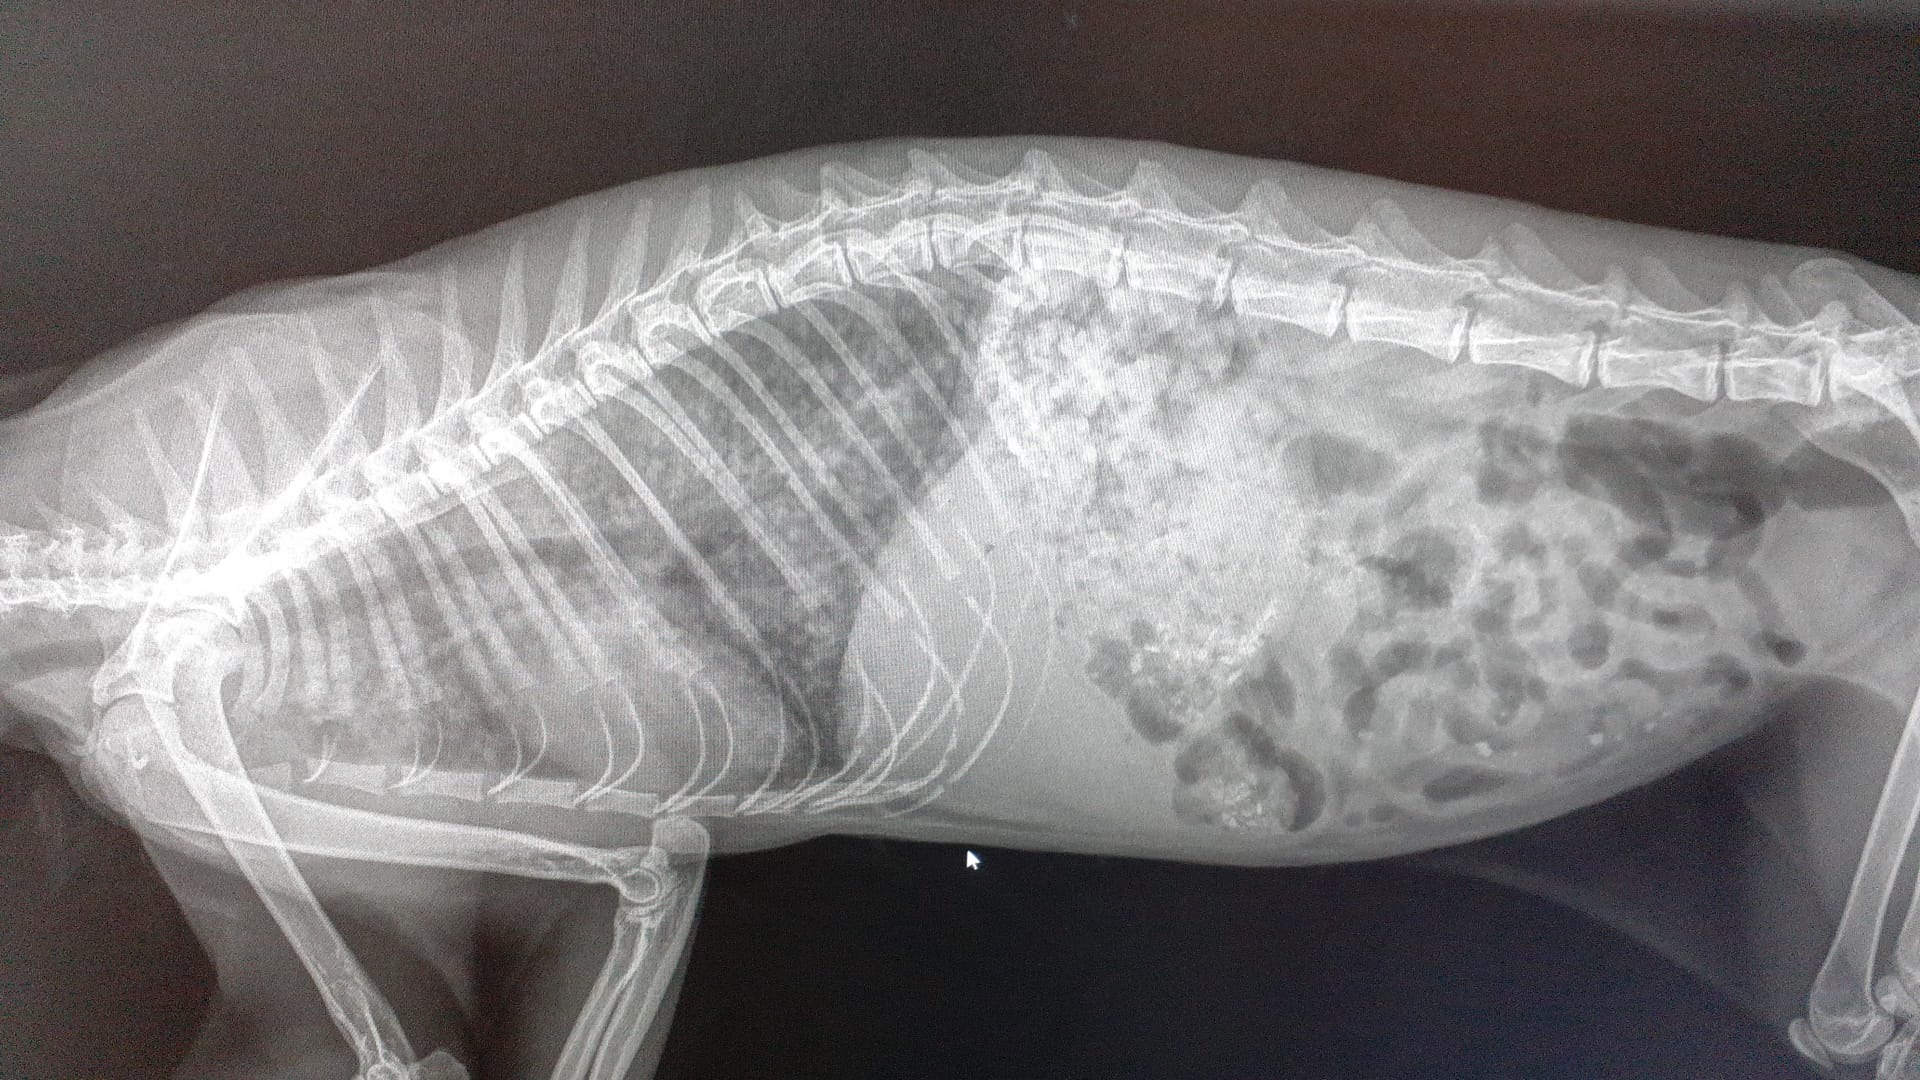

Due giorni fa, la situazione è precipitata: Sissi è stata ricoverata d'urgenza presso la Clinica Primavera di Palermo per insufficienza respiratoria e polmonite causata da un' infestazione massiva di parassiti polmonari ( i maledetti Strongili)

Oggi, Sissi è finalmente fuori pericolo, ma la ripresa sarà lunga e lenta, e deve restare in gabbia ossigeno per riprendersi completamente. Povera anima indifesa.